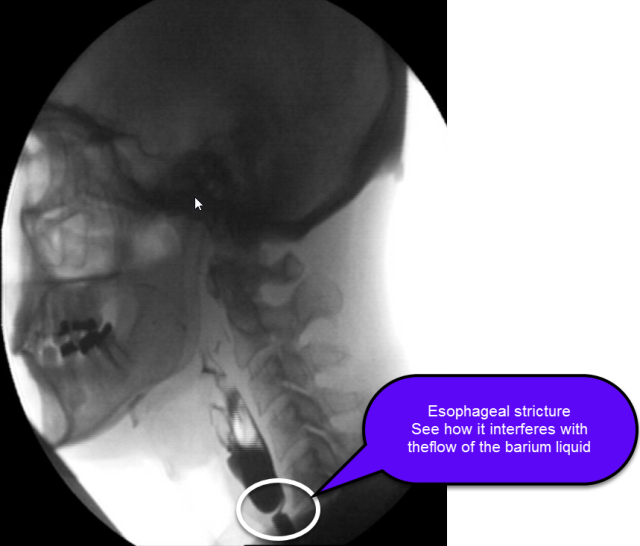

From www.researchgate.net

Barium xray of a benign esophageal stricture. Download Scientific Medical Term For Esophageal Stricture It often presents as dysphagia, commonly described by. an esophageal stricture is a gradual narrowing of the esophagus, which can lead to swallowing difficulties. an esophageal stricture occurs when your esophagus narrows, usually due to an illness or injury. an esophageal stricture refers to the abnormal narrowing or tightening of the esophagus. The esophagus is a tube.. Medical Term For Esophageal Stricture.